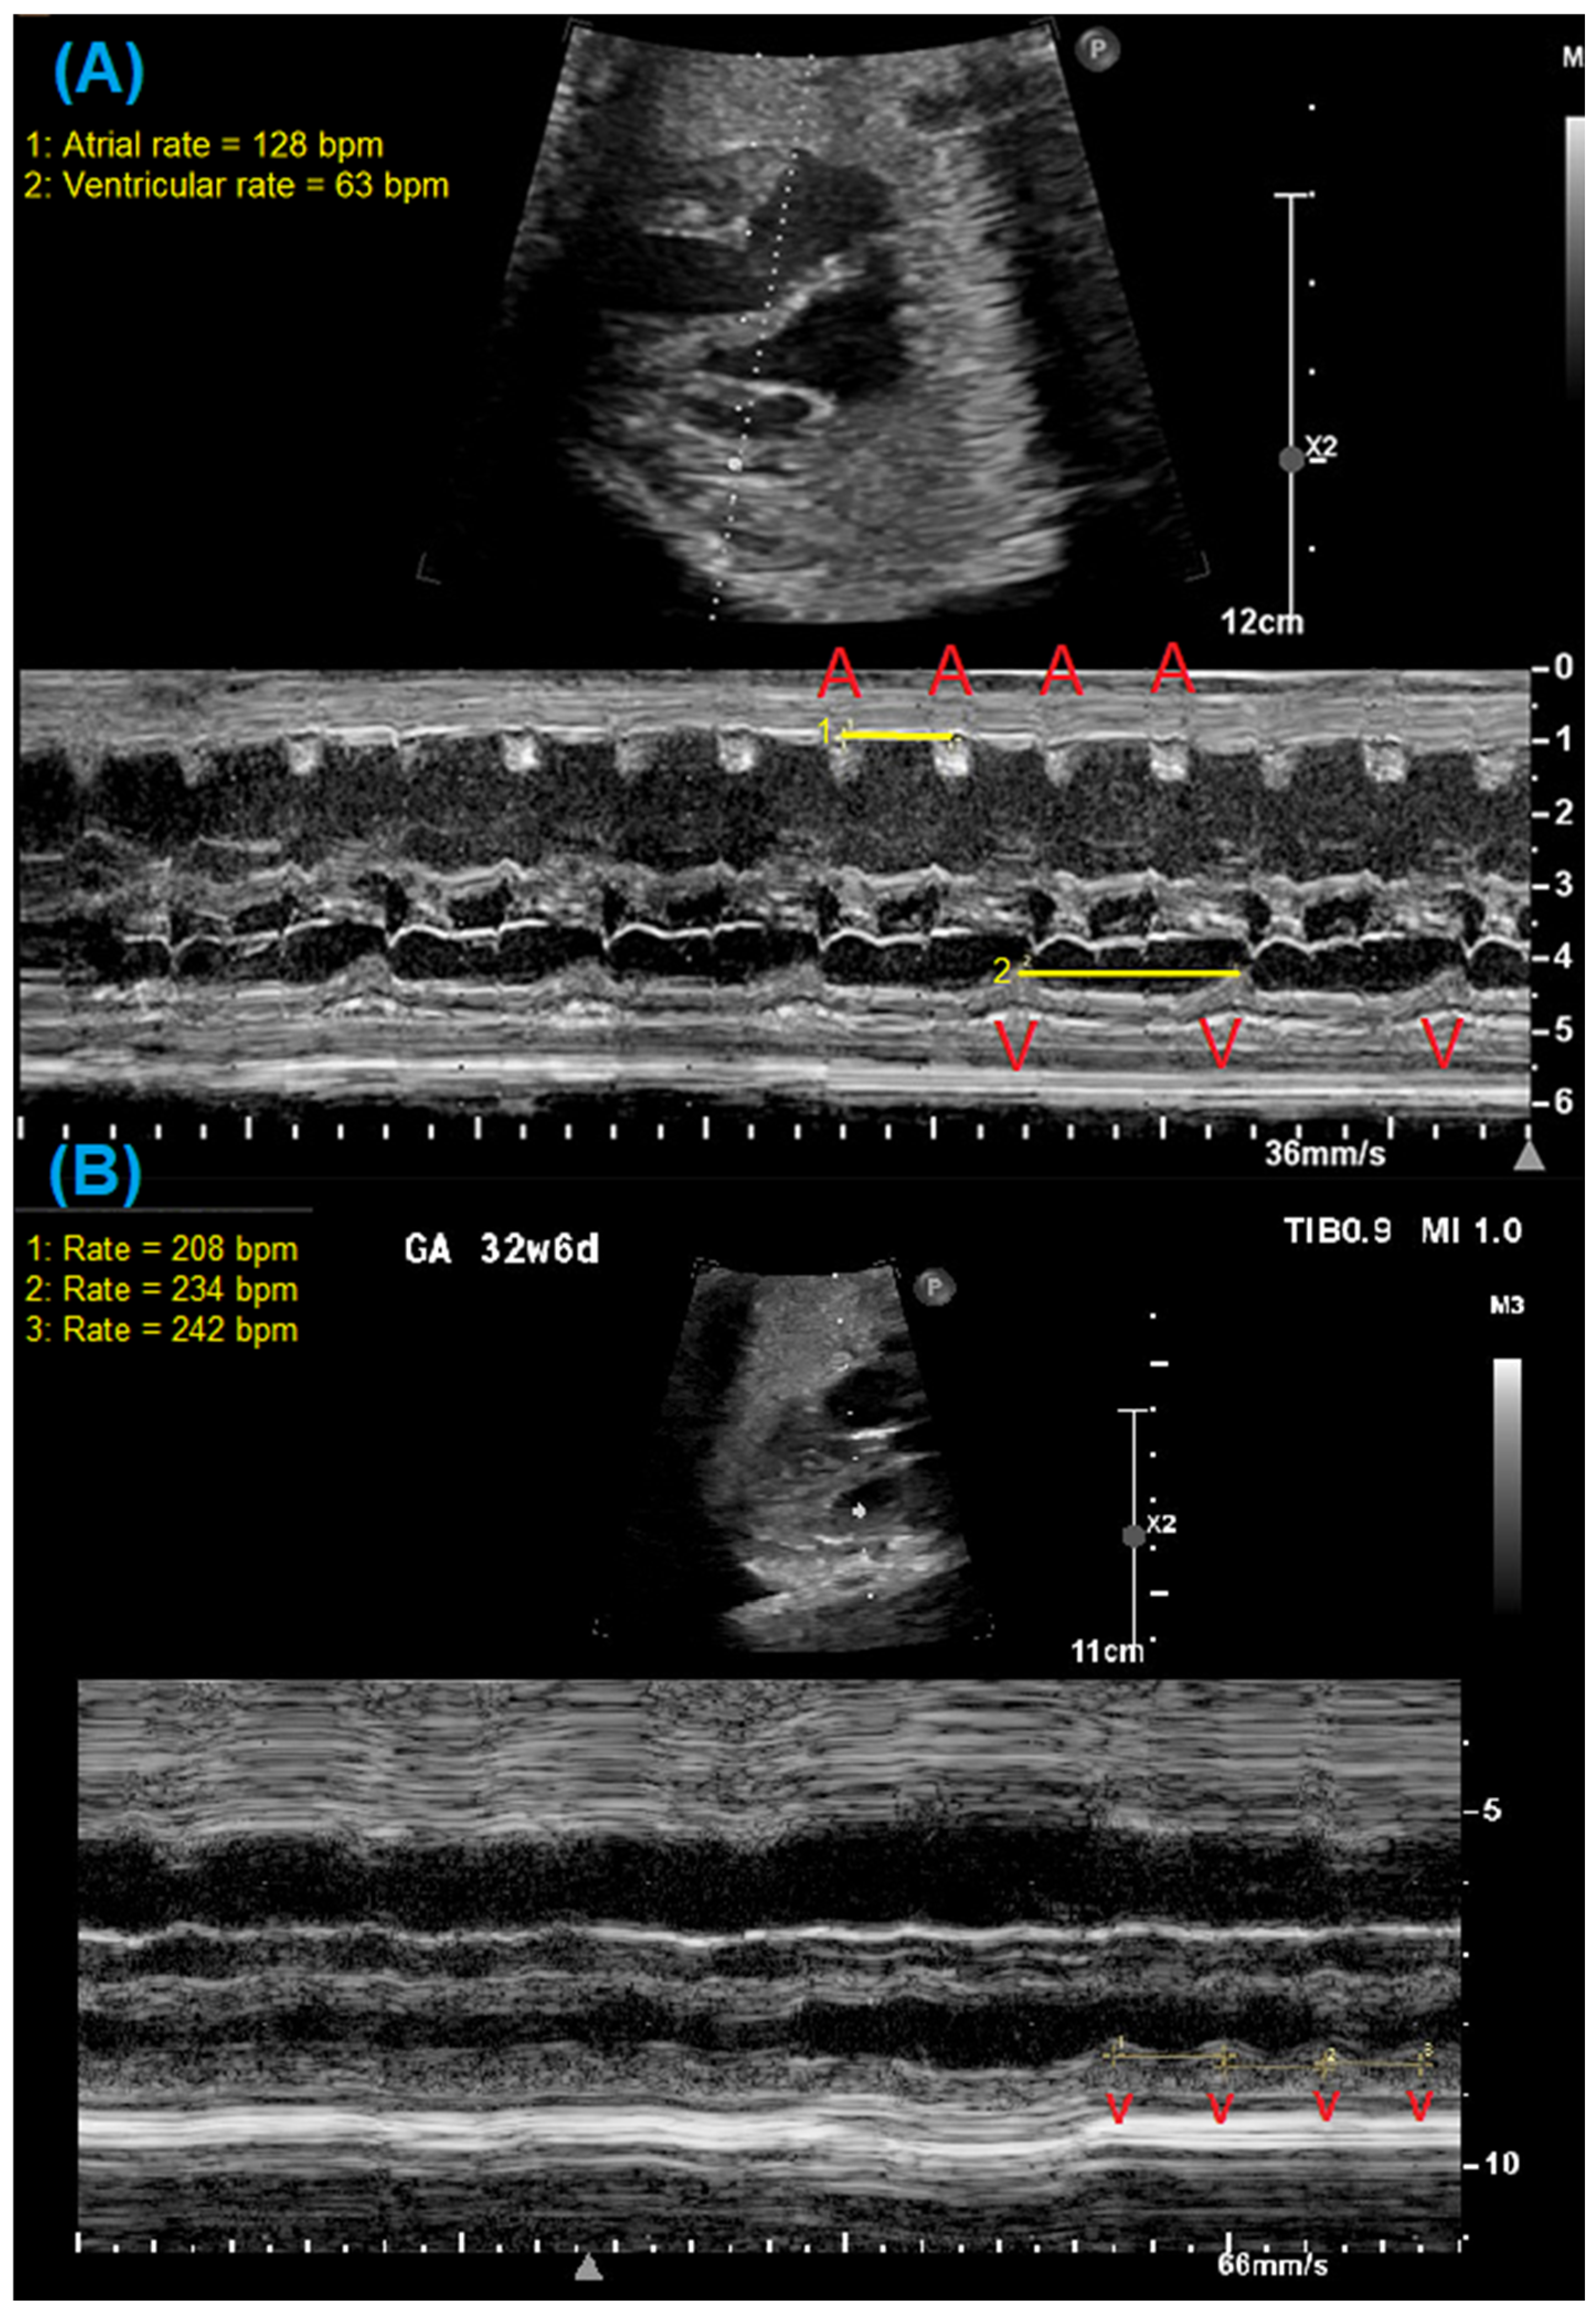

2. Fetal Diagnosis of Long QT Syndrome